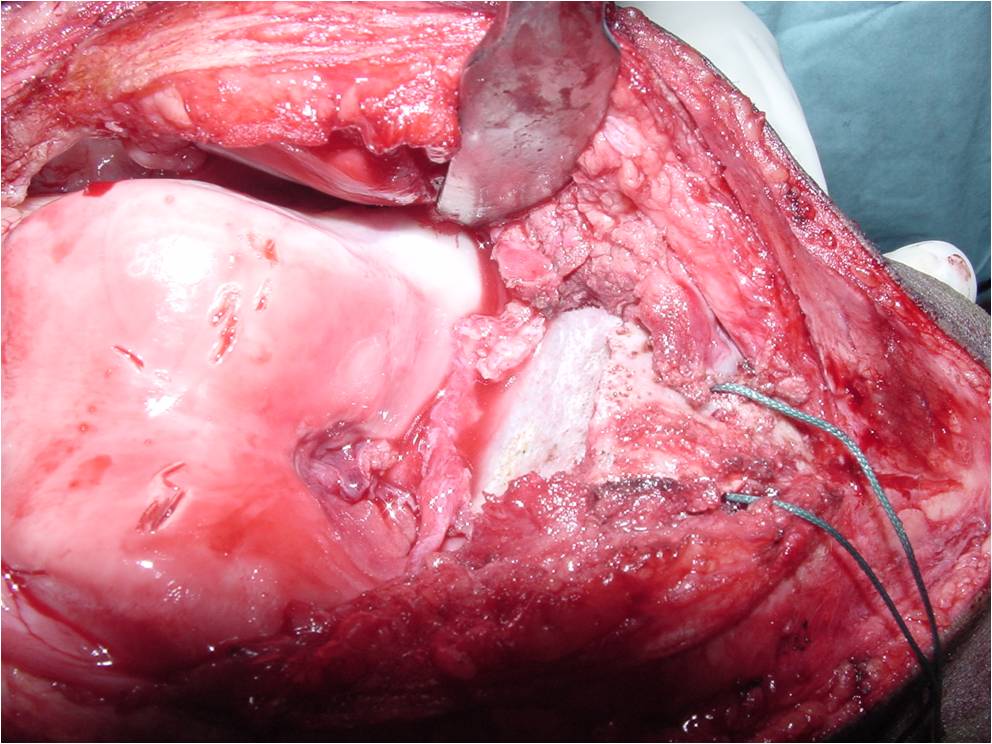

- Treatment of a Chondroblastoma of Proximal Humerus with Intralesional Curettage Resection, Cryosurgery and Bone Grafting

- intralesional curettage resection and bone grafting most common treatment

- Cement and internal fixation may also be used to fill the defect after removal for selected patients

- Local adjuvants such as cryosurgery (liquid nitrogen application) may be considered to decrease the risk of local recurrence